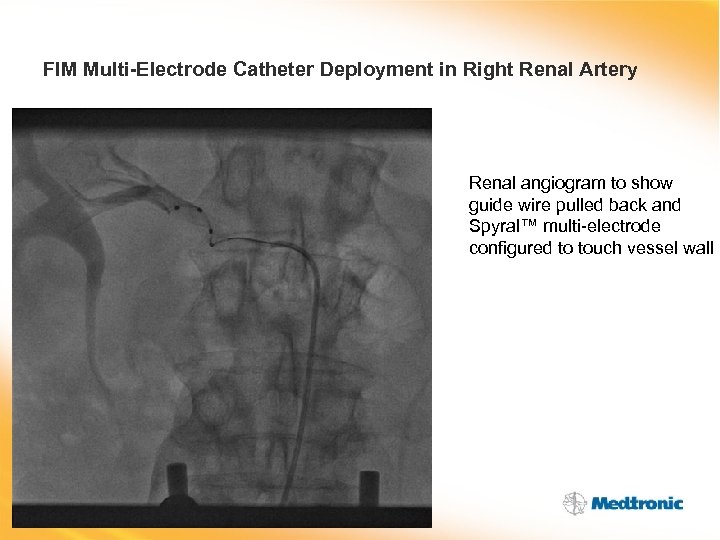

FIM Multi-Electrode Catheter Deployment in Right Renal Artery Renal angiogram to show guide wire pulled back and Spyral™ multi-electrode configured to touch vessel wall

FIM Multi-Electrode Catheter Deployment in Right Renal Artery Renal angiogram to show guide wire pulled back and Spyral™ multi-electrode configured to touch vessel wall